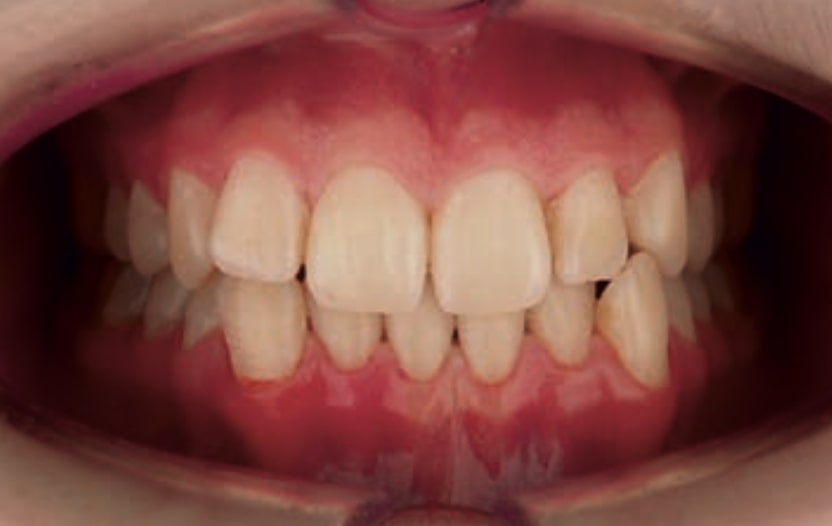

Chief complaint: The patient, a 19-year-old woman, was evaluated to undergo orthodontic treatment using the Angel Aligner Pro system. She presents with a skeletal Class III, mesofacial, with a dental Class III malocclusion and a 2 mm deviation of the lower midline to the left. Teeth 33 and 43 are out of the arch and cortical bone, with a crossbite issue on tooth 33. Fortunately, no functional issues affecting swallowing or breathing have been detected. The patient’s motivation for starting treatment was a general review of her dental and aesthetic health. The soft tissue analysis reveals mandibular protrusion that influences her facial profile. This diagnosis highlights the need for a comprehensive approach to address dental and skeletal misalignments, improving both the patient’s functionality and facial aesthetics.

- Dental Class III, 2 mm deviation of the lower midline to the left. 33 and 43 out of the arch and the cortical bone.

- Crossbite of 33.

- Soft Tissue Analysis: Jaw protrusion